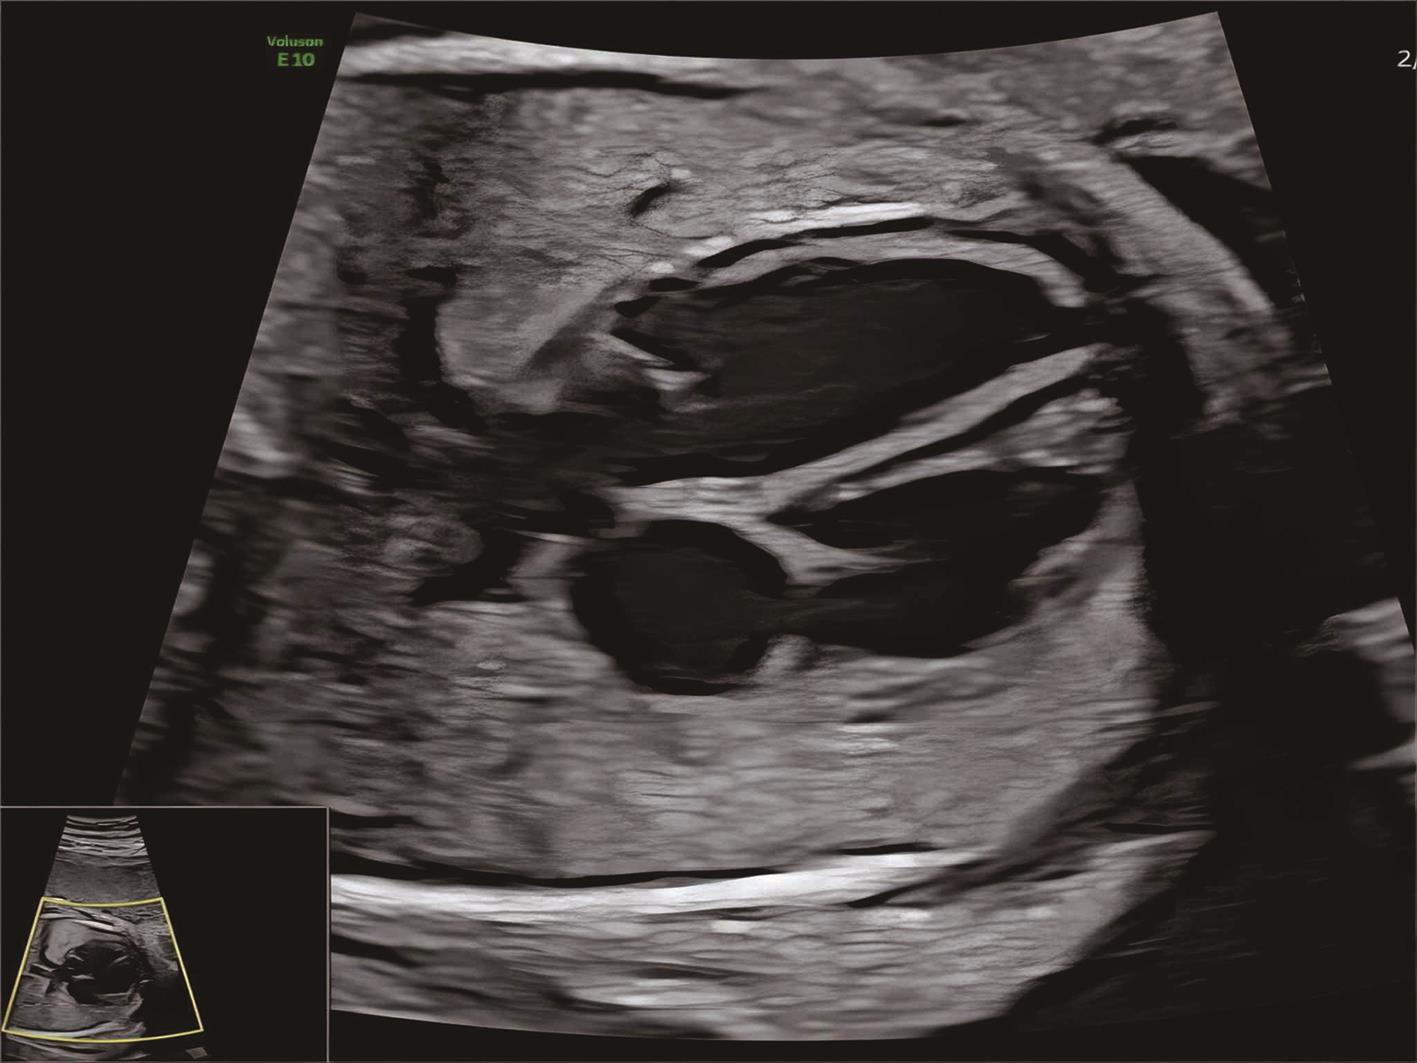

• 胎儿心脏定量分析技术评价妊娠期肝内胆汁淤积症孕妇胎儿心室收缩功能

2024, 49(1):85-90. DOI: 10.13406/j.cnki.cyxb.003377

摘要 (50) HTML (24) PDF 1.70 M (137) 评论 (0) 收藏

摘要:目的 探讨妊娠期肝内胆汁淤积症(intrahepatic cholestasis of pregnancy,ICP)对胎儿心室收缩功能的影响,为临床早期发现ICP胎儿心功能异常提供依据。方法 选取2022年7月至2023年4月于川北医学院附属医院就诊孕妇67例,孕周27~40周,其中ICP孕妇29例(ICP组),正常孕妇38例(对照组)。应用胎儿心脏定量分析(fetal heart quantification,Fetal HQ)软件测量胎儿心室收缩功能,包括纵向收缩功能:左、右心室整体纵向应变(global strain,GLS)、间隔壁应变(sept wall strain,SWS)、侧壁应变(free wall strain,FWS);横向收缩功能:左、右心室24节段短轴缩短率(fractional shortening,FS);整体收缩功能:左、右心室面积变化分数(fetal area change,FAC)、左心室射血分数(ejection fraction,EF)。结果 ICP组纵向收缩功能指标左、右心室GLS、SWS、FWS均低于对照组,差异有统计学意义(P<0.05);两组间横向收缩功能指标左、右心室24节段FS比较,差异均无统计学意义(P>0.05);ICP组整体收缩功能指标左、右心室FAC均低于对照组,差异有统计学意义(P<0.05),而两组间左心室EF比较,差异无统计学意义(P>0.05)。结论 在宫内高胆汁酸环境下,ICP胎儿心脏左、右心室整体及纵向收缩功能明显受损,横向收缩功能未见明显改变;并且与传统心脏功能评价指标左心室EF相比,FAC可以更加敏感地反映胎儿心脏整体功能的改变。